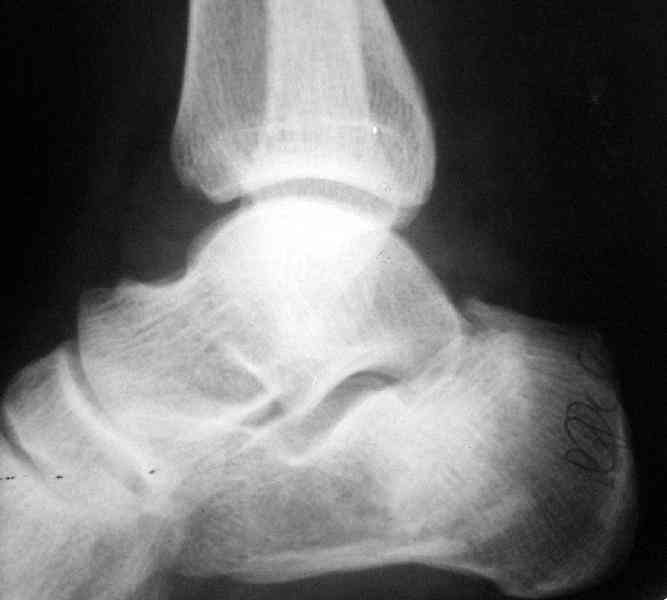

Если я правильно понял, вы хотели спросить: "Что делать с кистой, и как на этом фоне выполнять репозицию и фиксацию перелома?"

Я думаю, что для начала нужно выполнить КТ пяточной кости и определиться с границами полости. Не исключено, что отрывной перелом верхнего полюса бугра носит патологический характер (верхняя стенка кисты).

Its a comminuted one.

Сустав похоже интактен, киста под вопросом,даже при наличии опыта остесинтеза пластиной, в данном случае выведение правильного угла и фиксация спицами более чем достаточно, да и намного спокойнее сон у хируга.

Перелом безусловно внутрисуставной. Киста-не киста принципиального значения не имеет.